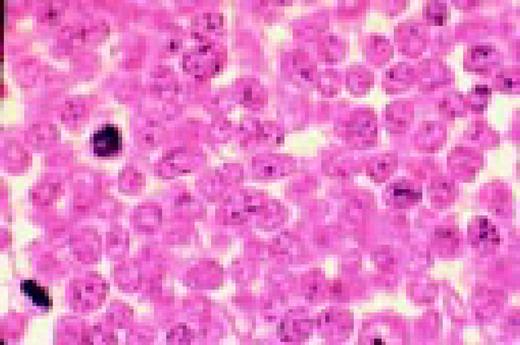

Slide L41

Multiple myeloma, bone marrow aspirate. The cytoplasmic periphery of these cells has a much more intense pink stain, therefore the names flaming myeloma cells or flaming plasma cells.FIG41